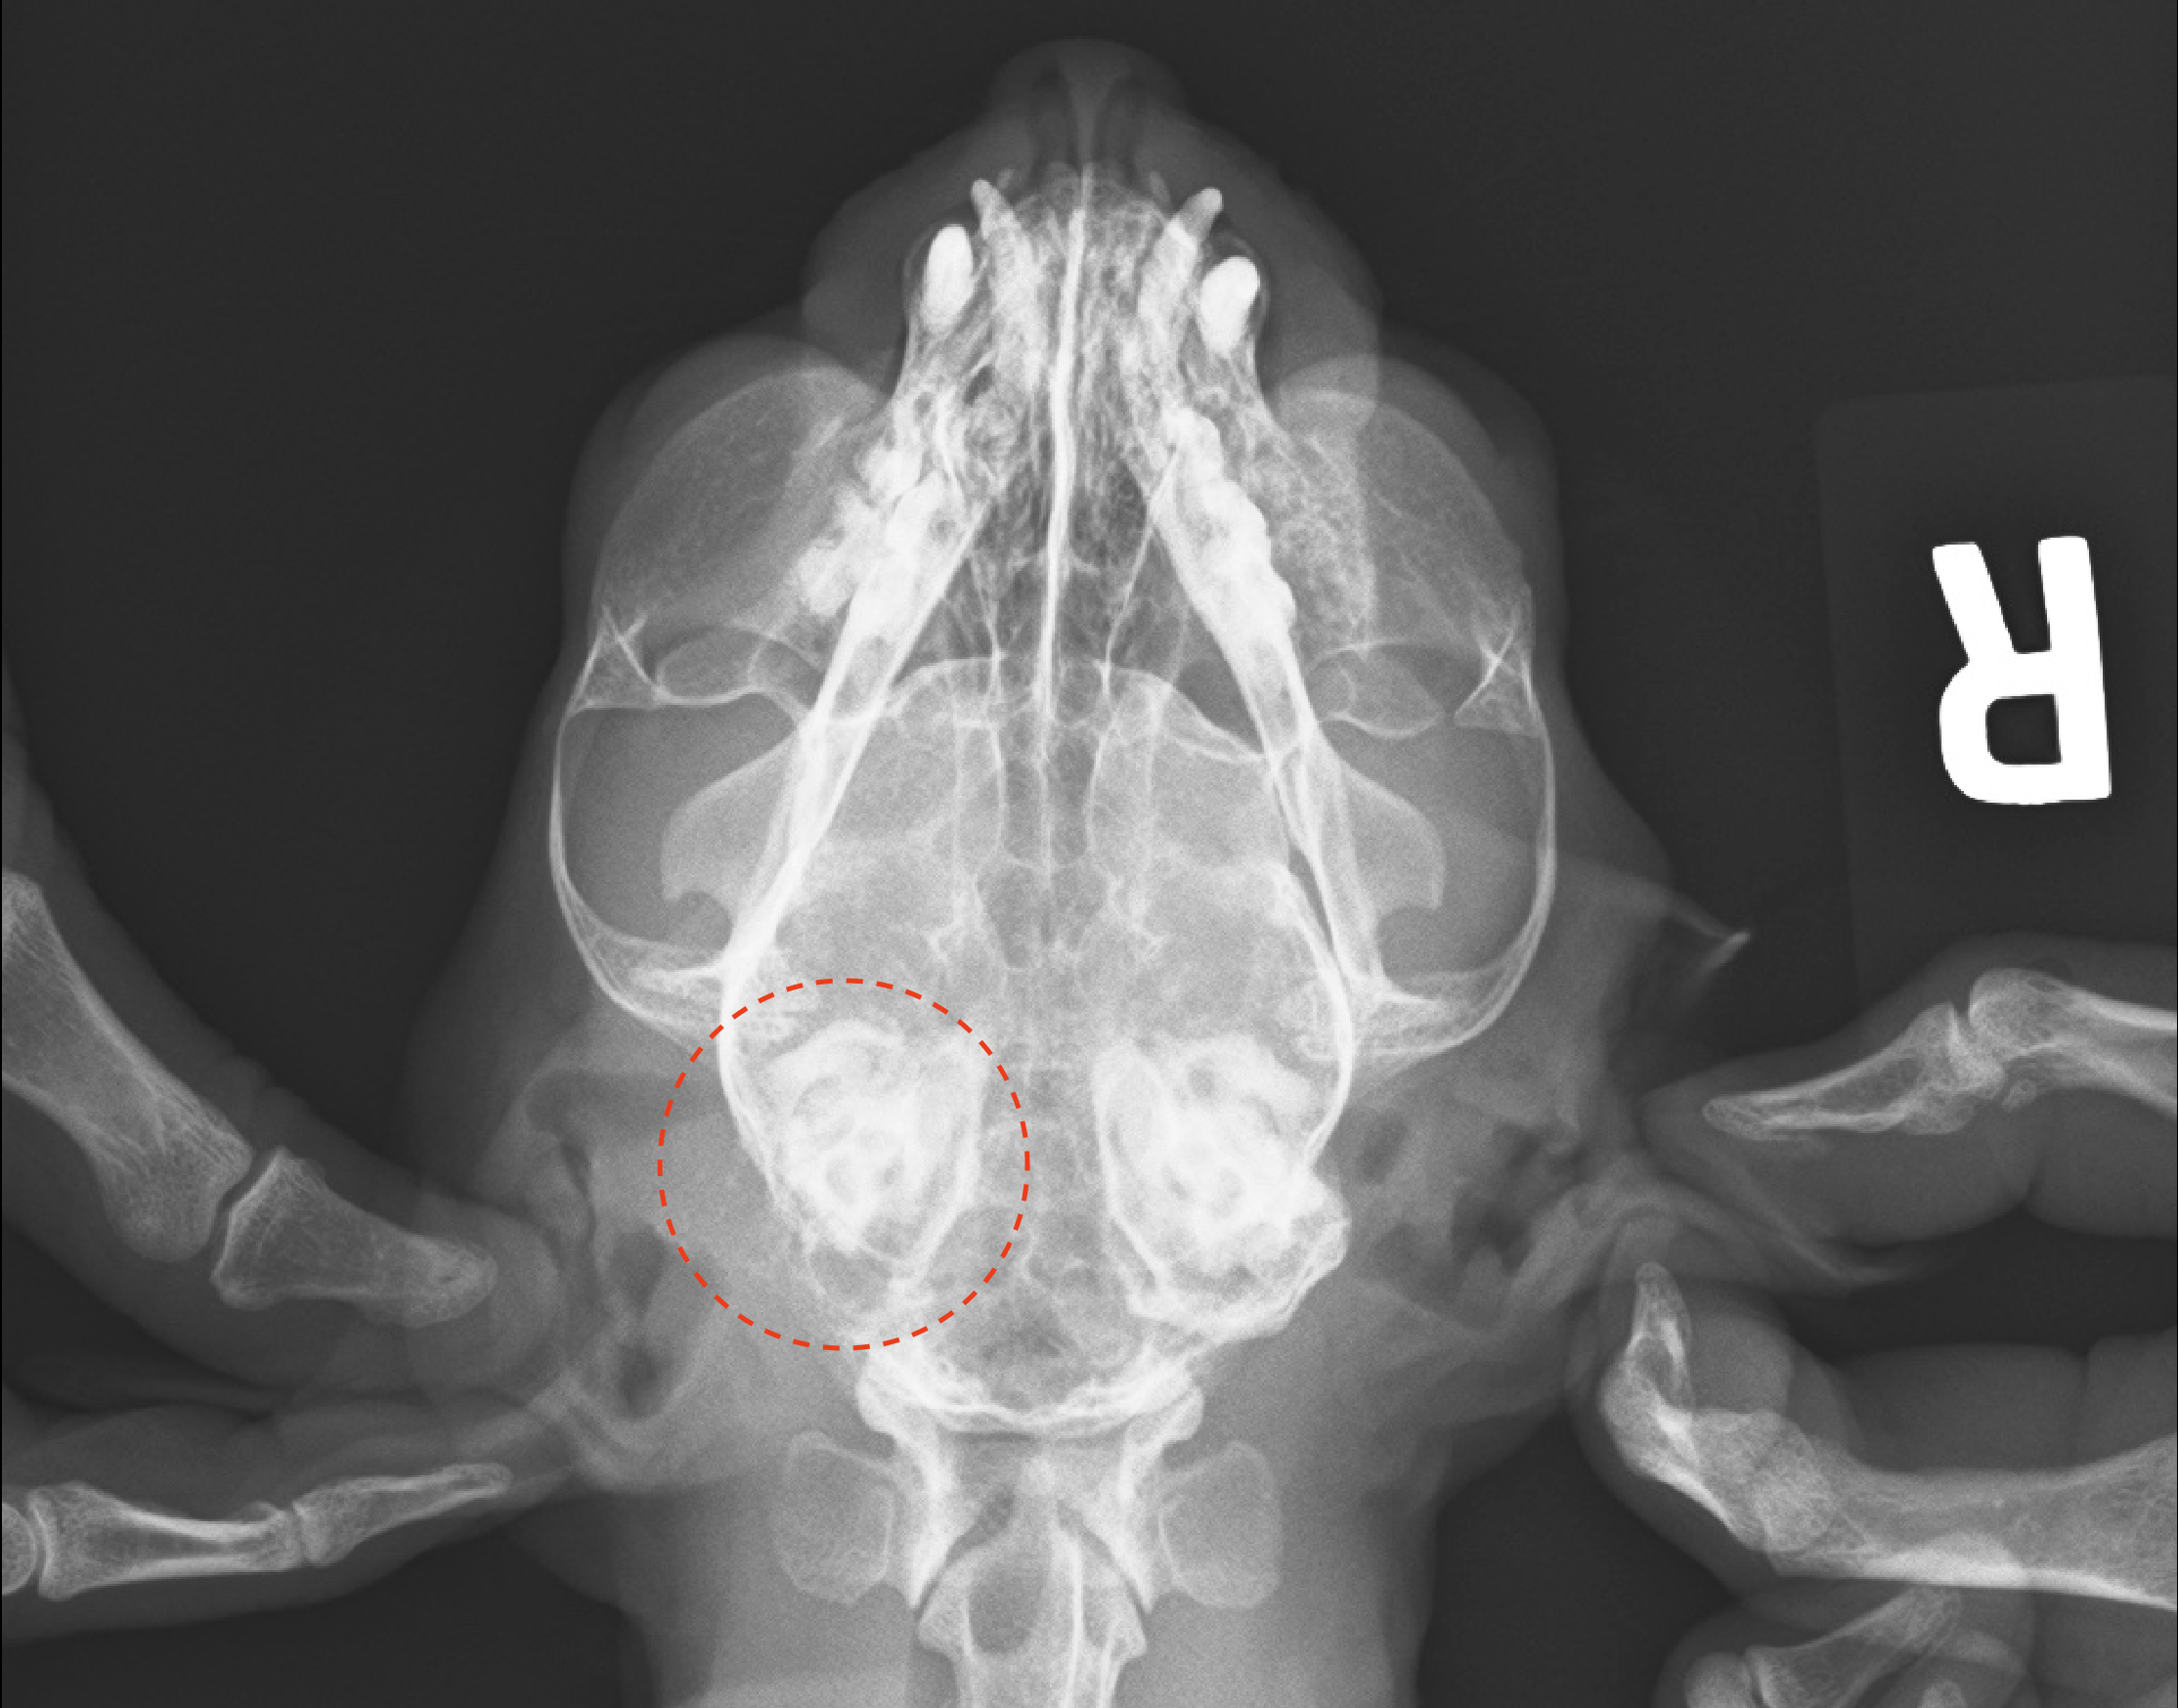

お迎えのタイミングで当日わかった所見として 左耳中耳炎からの前庭疾患 という診断が出た。

左耳がかなり汚れていたのと、

レントゲンでも左側の耳の骨が溶けているような見え方をしていることから外耳炎または中耳炎はほぼ確定、

さらに発作(眼振)やふらつきといった症状が継続しており前庭疾患の疑いが強いということだった。

前庭疾患の特徴としては平衡感覚が狂って気持ち悪い状態が続くもの。

実際に出ている症状もまさにそれに起因する感じなのでほぼ決まり。

また、眼振というのは異常がある方向に引っ張られることが多いらしく、

眼振の動画をよくみると黒目が左耳方向に引っ張られてからゆっくり中央に戻るような感じで、

まさに左耳が原因と思われる。